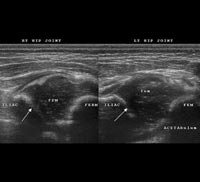

CDH